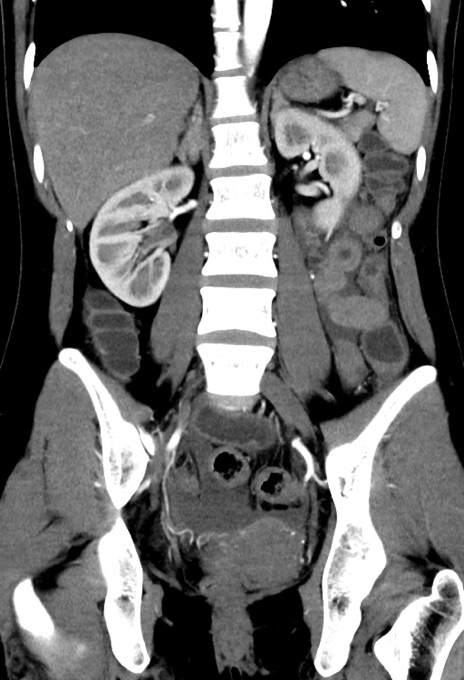

症例17(冠状断像)

【症例】20歳代女性

【主訴】嘔吐、下腹部痛

【現病歴】昨日夕食後に嘔吐し下腹部痛が出現。本日になっても嘔吐持続し改善しないため来院。

【身体所見】意識清明、BT 37.2℃、BP 108/67mmHg、腹部:平坦、やや硬、下腹部正中から右にかけて圧痛あり、反跳痛軽度あり、tapping pain(+)。

【データ】WBC 13600、CRP 14.94